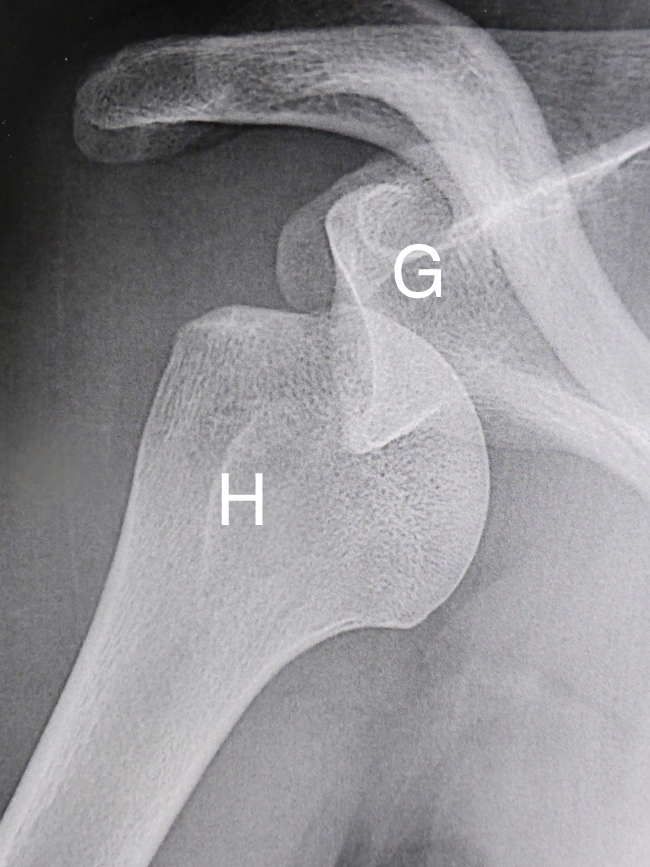

Normalement, l’articulation entre l’humérus et omoplate est stable

Sur cette radiographie de face d’une épaule normale, la tête de l’humérus (H) est bien en face de la glène de l’omoplate (G).

c’est-à-dire que les deux surfaces articulaires restent bien l’une en face de l’autre dans toutes les circonstances.